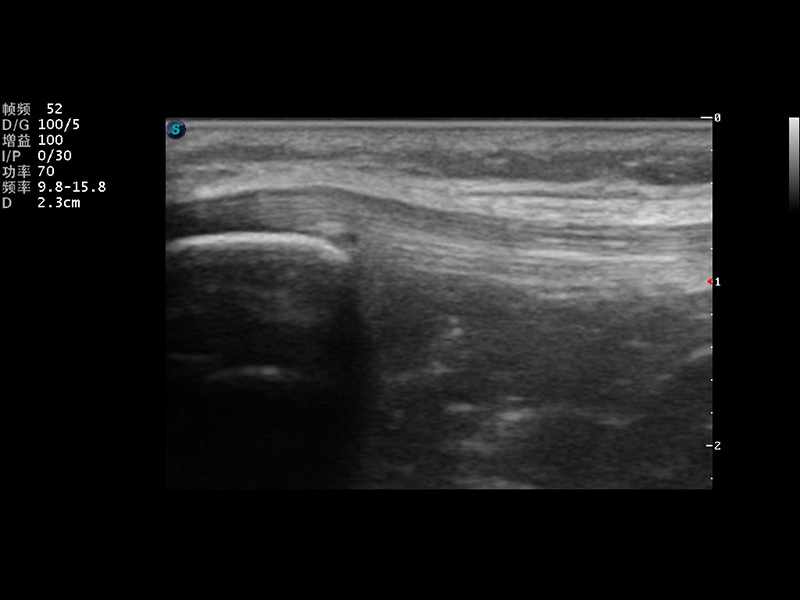

S9便携式彩色多普勒超声诊断仪是乐玩lewin国际研发的高端便携彩超设备,外观设计新颖、产品性能卓越。S9在便携超声领域采用了突破传统的触摸屏交互设计,并以先进的软件硬件技术和设计理念,为您带来清晰的图像质量、稳定的工作性能和便捷的操作体验。

成像技术